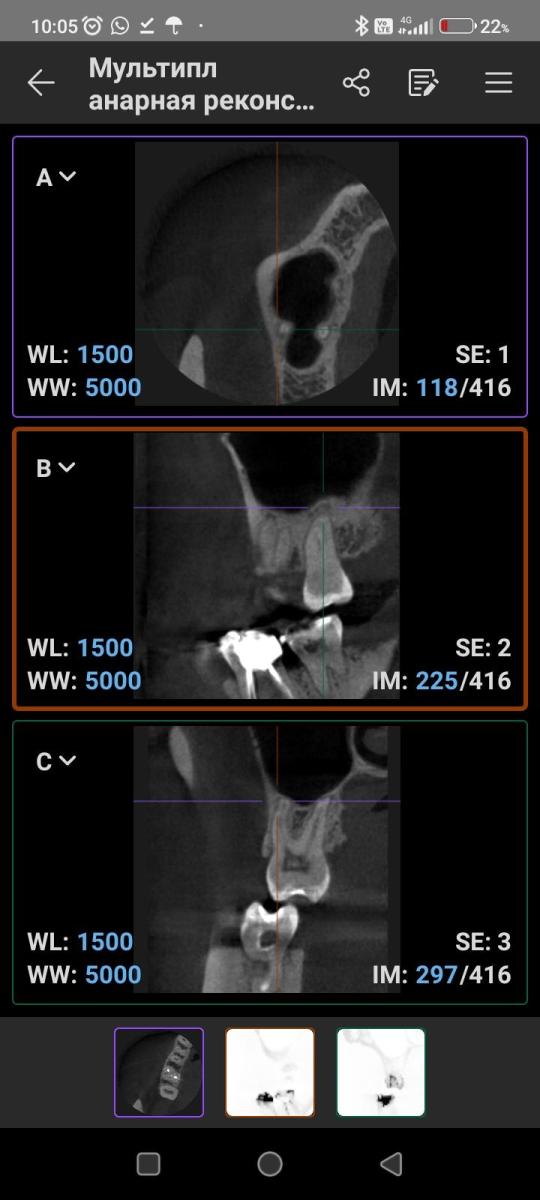

Что может означать затемнение на верхушке корней 17 зуба? Есть ли дентикли в пульпе? Есть постоянная не острая болезненность по ходу верхнечелюстной ветви. Может ли источником боли быть 17 зуб?

"Что может означать затемнение на верхушке корней 17 зуба?"

"Есть ли дентикли в пульпе?"

"Может ли источником боли быть 17 зуб?"